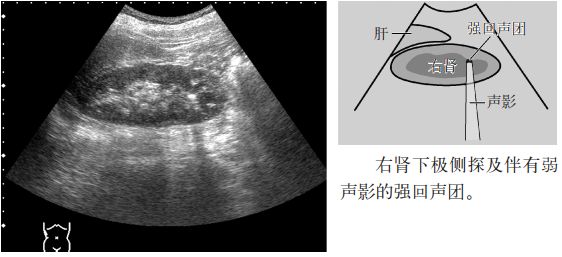

图2 肾结石

注意:小于5mm的肾结石几乎无声影,但是,超声入射角度微妙的变化可以显示点状高回声和声影。因此,平静呼吸时或改变经肋间扫查的位置,有时会出现声影,因此,不仅要在吸气时观察,还应在呼气时或改变经肋间扫查的位置时进行观察。